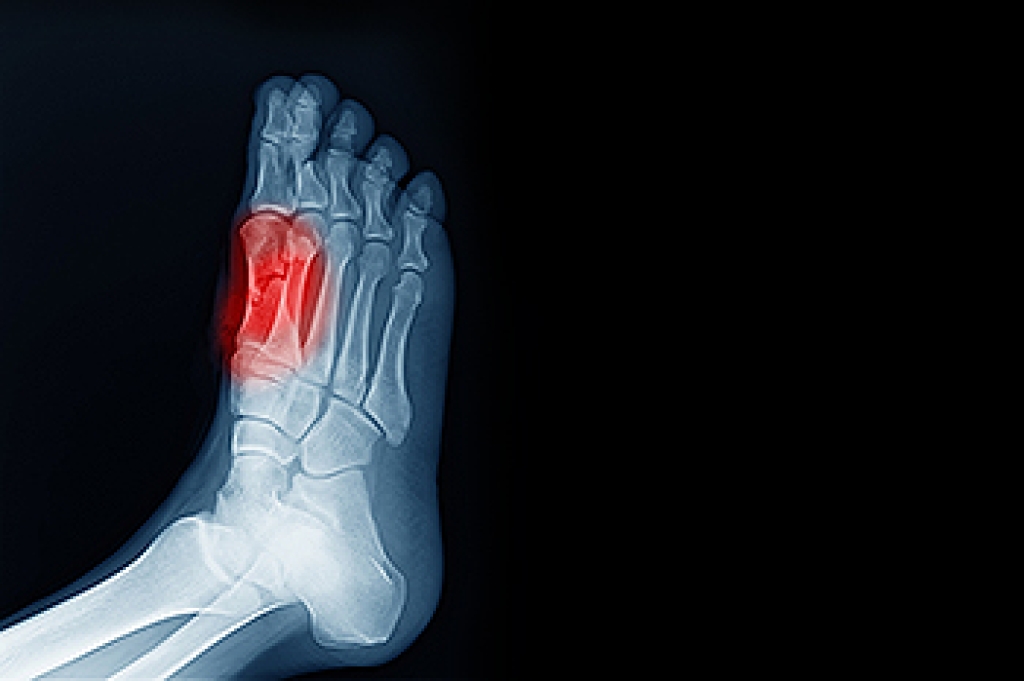

Inflammatory arthritis is a group of conditions in which the immune system causes ongoing joint inflammation. Common types include rheumatoid arthritis, psoriatic arthritis, ankylosing spondylitis, and gout. These conditions often affect the feet and ankles early, leading to pain, swelling, stiffness, and changes in joint structure. Over time, inflammation can alter foot shape, increase pressure points, and make walking difficult. Proper foot care helps reduce discomfort and protect mobility. Wearing supportive footwear with cushioning and adequate toe space can limit joint stress, while custom orthotics may improve alignment and pressure distribution. Gentle movement, stretching, and pacing daily activities can also help manage symptoms. Swelling and joint changes increase the risk of skin irritation, calluses, and nail problems, making routine foot checks important. If foot pain, deformity, or walking difficulty develops, it is suggested that you see a podiatrist for evaluation and appropriate treatment.

Arthritis is a term that is commonly used to describe joint pain. The condition itself can occur to anyone of any age, race, or gender, and there are over 100 types of it. Nevertheless, arthritis is more commonly found in women compared to men, and it is also more prevalent in those who are overweight. The causes of arthritis vary depending on which type of arthritis you have. Osteoarthritis for example, is often caused by injury, while rheumatoid arthritis is caused by a misdirected immune system.

Arthritic symptoms range in severity, and they may come and go. Some symptoms stay the same for several years but could potentially get worse with time. Severe cases of arthritis can prevent its sufferers from performing daily activities and make walking difficult.

If you suspect your arthritis is affecting your feet, it is crucial that you see a podiatrist immediately. Your doctor will be able to address your specific case and help you decide which treatment method is best for you.